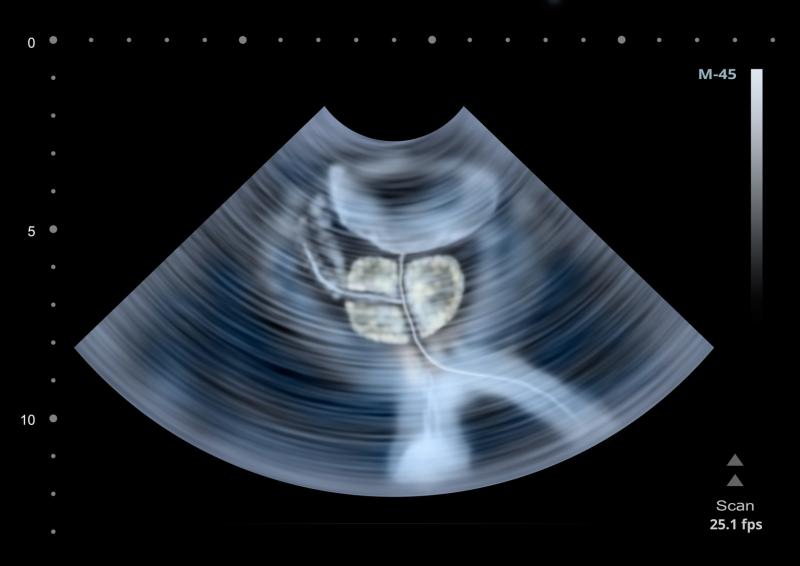

In prostate cancer patients, retzius-sparing robotic-assisted radical prostatectomy (RS-RARP) yields better continence outcomes compared with conventional RARP, a recent study has found.